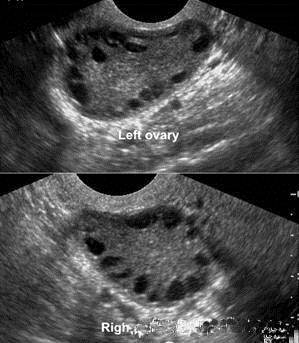

2.超声检查 见卵巢增大,包膜回声增强,轮廓较光滑,间质回声增强;一侧或两侧卵巢各有12个及以上直径为2~9mm无回声区,围绕卵巢边缘,呈车轮状排列,称为“项链征"(图29-7)。连续监测未见主导卵泡发育及排卵迹象。

图29-7 PCOS的超声图像(项链征)